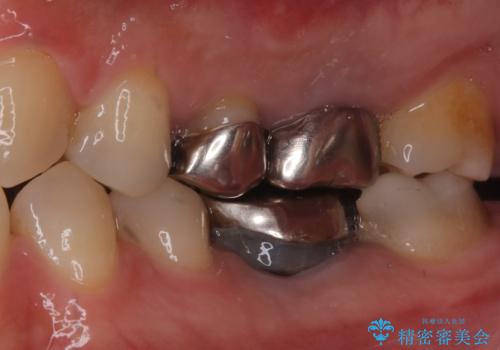

- お口の中にある銀歯を全てなくして、白く健康的な状態にしたい」という主訴でご来院されました。長年使用してきた複数の銀歯は、経年劣化により適合が悪くなっており、一部では内部で二次カリエス(虫歯の再発)も認められました。

銀歯の除去と精密な再治療: 古い銀歯を一つひとつ丁寧に取り外し、内部の虫歯を徹底的に除去。神経を保護するための処置を行った上で、適合性を極限まで高めるために精密な型取りを行いました。